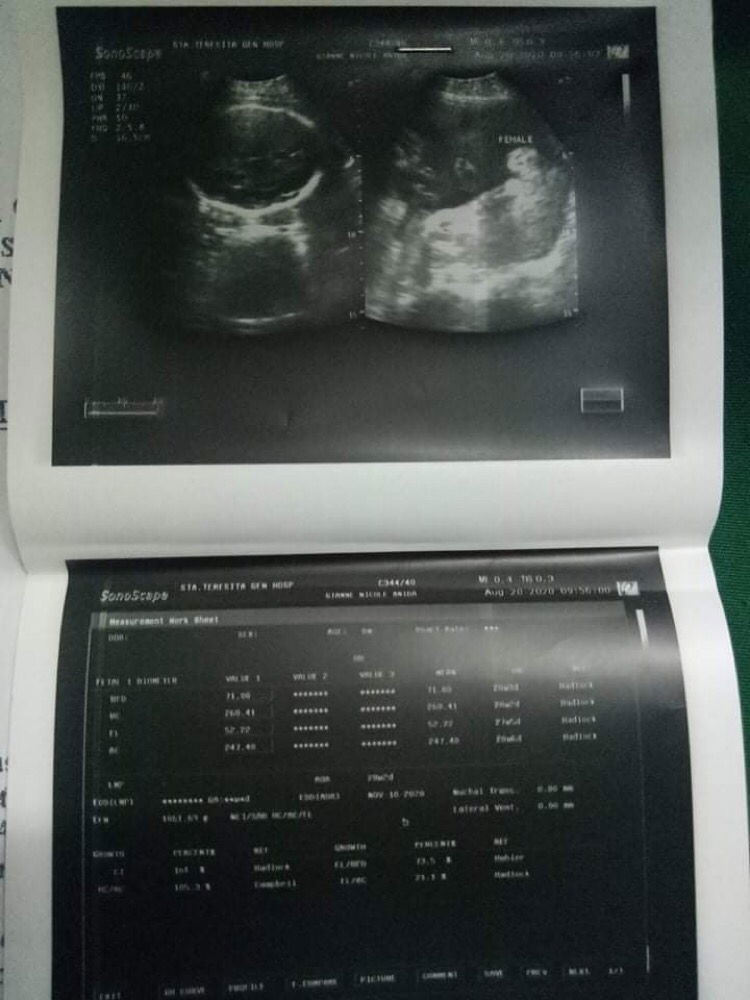

Edd: Oct. 20, 2020 DOB: Sept. 28, 2020 Skl mga momsh unexpected lhat nangyre bale sept. 20 sunday nglkad kmi n mister ppunta at pblik hbng nsa daan nkraramsm ako pnnkit ng puson, pguwi nmin ng pm ako sa center at cnbi ko ung mga nraramdamn ko then they asked me n pmnta to check fast forward po tau😅 3cm nko at 34 weeks plng tinkbo ako s hospital at nging 5cm then n admit 6pm umokei nko pro d pnauuwi dhl open n cervix ko hnggang ng wensday same 5cm and normal pdn ang feeling kya ngpplit nko umuwi. Pna BPS ako at ok c baby and kht ilbs k dw eh no need n ng incubator kso no sign of labor nko. Monday ng decide OB ko n putukin n pnubigan ko pro wla pdn at 7 to 8cm nko so ininduce labor nko by 10am ng monday 11am ska lng ng start ung labor ko untill 12:45 sobrang thankful ako d nyako pnhirapn ng sobrng tgal. Xnxa n ang haba n ng kwento ko sa mga momsh n d pa nanga2nak pray lng mkkaraos dn kau😊☝️